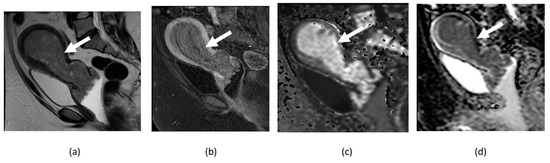

4.1. Cervical Cancer

- Haldorsen, I.S.; Lura, N.; Blaakær, J.; Fischerova, D.; Werner, H.M.J. What Is the Role of Imaging at Primary Diagnostic Work-Up in Uterine Cervical Cancer? Curr. Oncol. Rep. 2019, 21, 77. [Google Scholar] [CrossRef]

- Dappa, E.; Elger, T.; Hasenburg, A.; Düber, C.; Battista, M.J.; Hötker, A.M. The value of advanced MRI techniques in the assessment of cervical cancer: A review. Insights Imaging 2017, 8, 471–481. [Google Scholar] [CrossRef] [PubMed]

- Dashottar, S.; Preeth Pany, T.; Lohia, N. Role of apparent diffusion coefficient as a biomarker in the evaluation of cervical cancer. Indian J. Radiol. Imaging 2019, 29, 25–32. [Google Scholar] [CrossRef]

- Nakamura, K.; Joja, I.; Nagasaka, T.; Fukushima, C.; Kusumoto, T.; Seki, N.; Hongo, A.; Kodama, J.; Hiramatsu, Y. The mean apparent diffusion coefficient value (ADCmean) on primary cervical cancer is a predictive marker for disease recurrence. Gynecol. Oncol. 2012, 127, 478–483. [Google Scholar] [CrossRef] [PubMed]